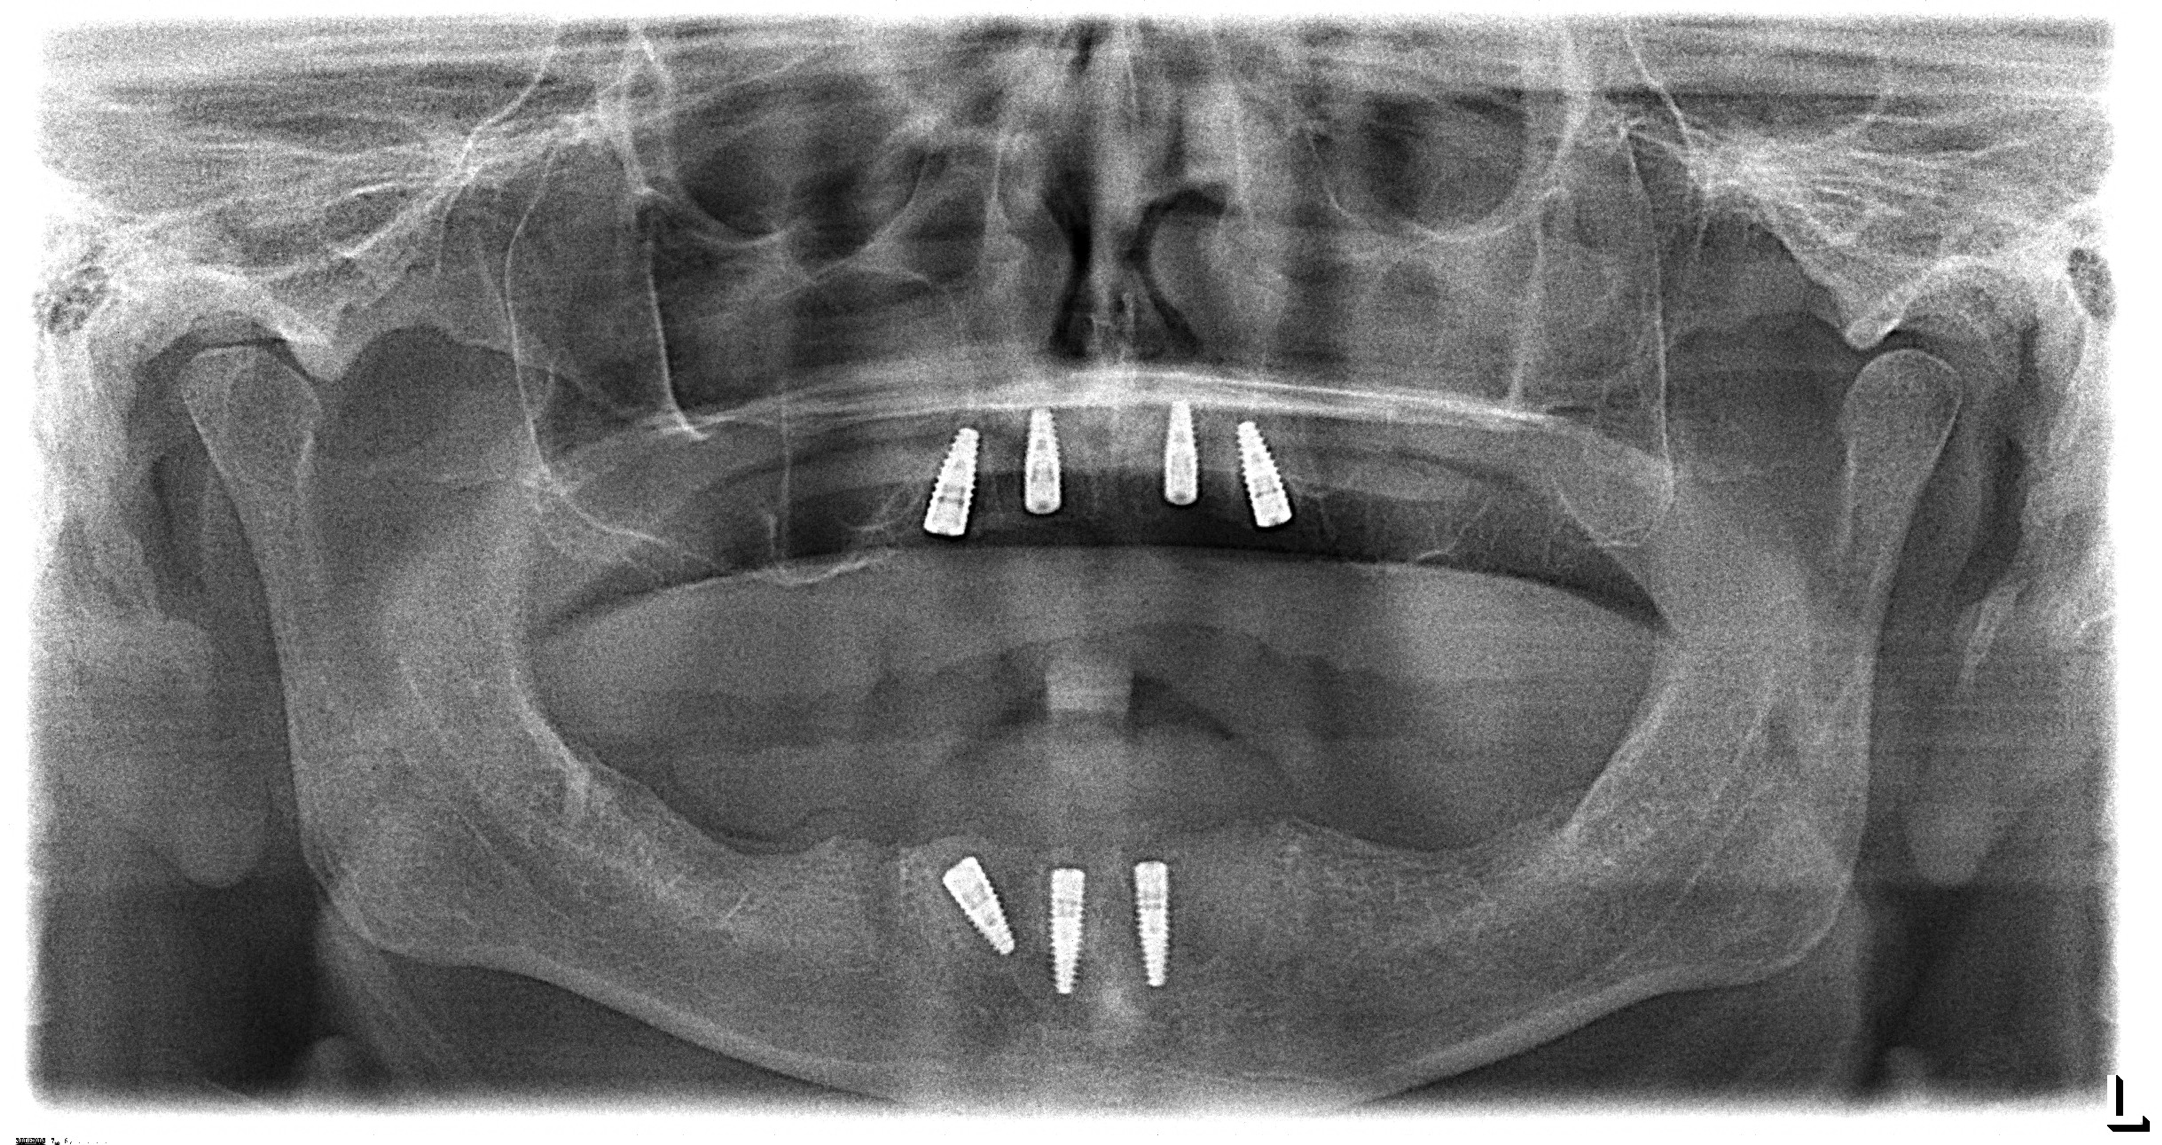

The second case was a 60-year-old man who primarily wanted new teeth. He had an All-on-4 case deemed appropriate by his surgeon. Unfortunately, proper preparation was not enacted, and the surgeon and restorative dentist were unfamiliar to each other. The surgeon evaluated the patient, decided an All-on-4 case would work, and sent the patient to the dentist for restoration. Figure 4 shows the result of this weak team dynamic. At the top there were four implants, and at the bottom there were three. The dentist did not feel the best result would come from using the three lower implants, so the patient was sent back to the surgeon with a recommendation that two more implants should be placed on the bottom. More implants were also desired on the top, but the sinuses would not allow it. If the surgeon and the dentist had discussed the case before the implants were placed, they could have proceeded further with the necessary implant placement much sooner.

Fig 4. Unworkable result due to lack of teamwork between the surgeon and the restorative dentist.

Figure 4